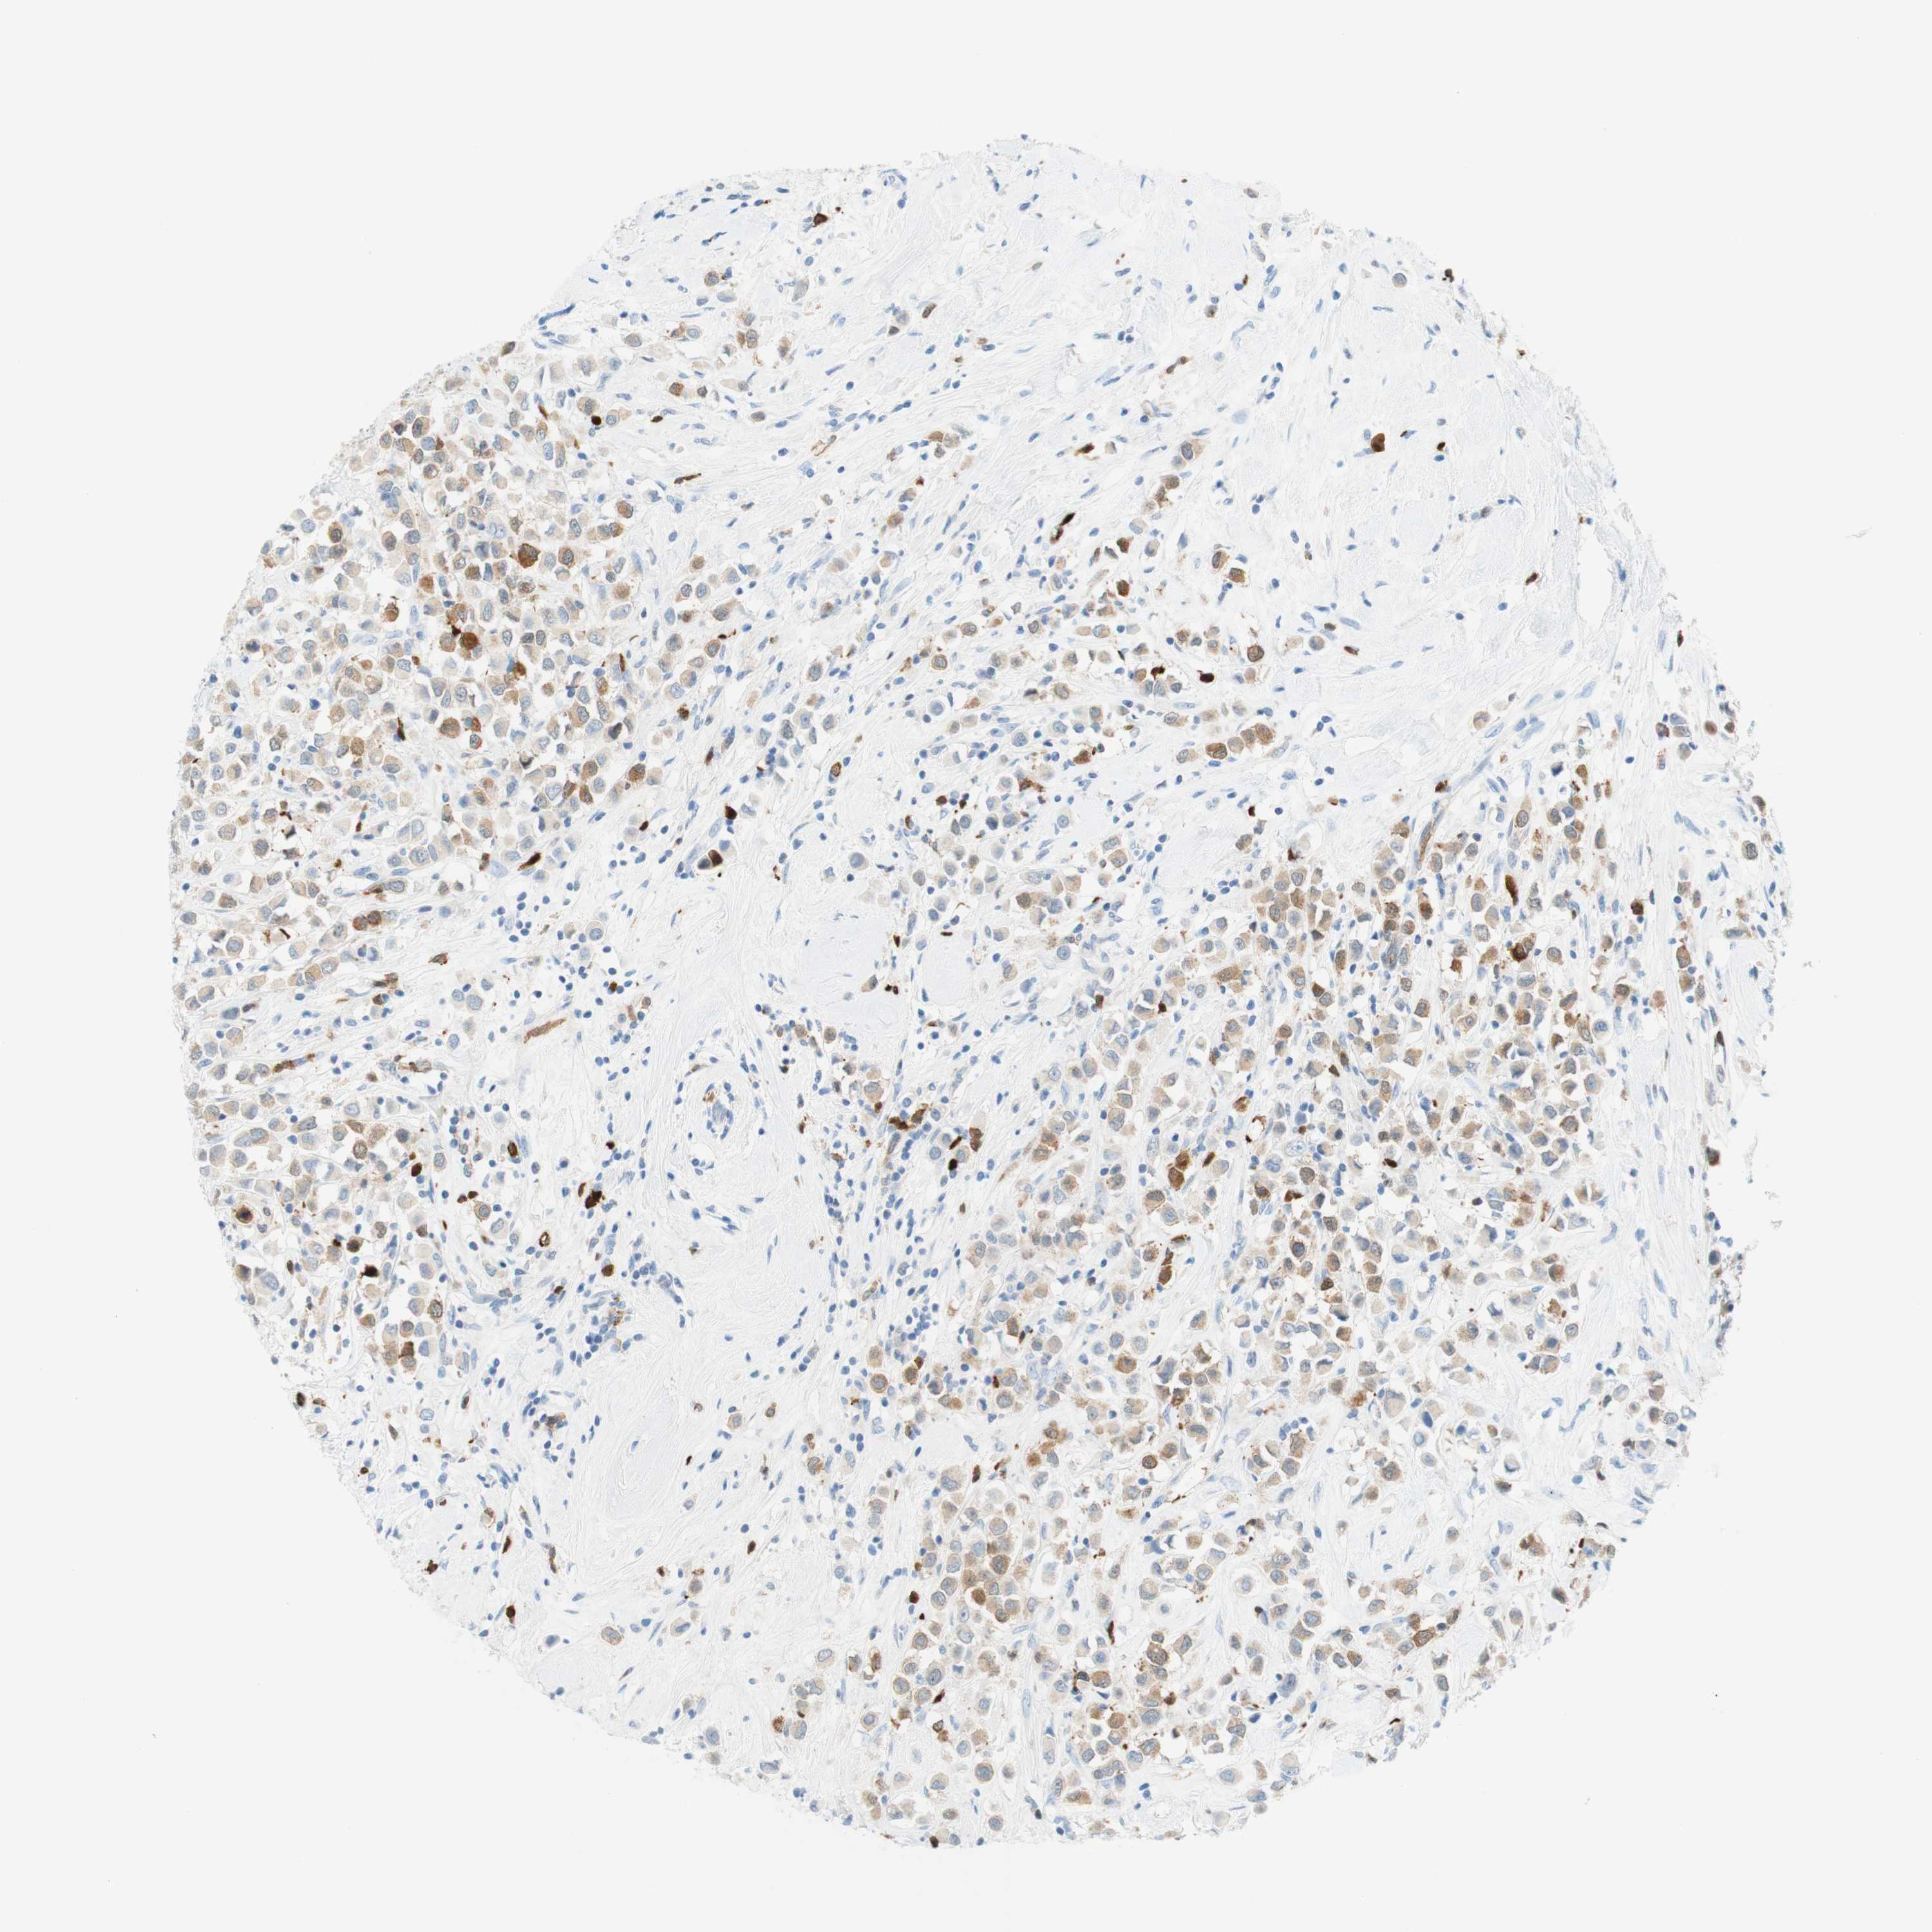

STMN1

CANCER BREAST CANCER Show tissue menu

BRCA TCGA BRCA VALIDATION PROTEIN EXPRESSION

ANTIBODIES

AND

VALIDATION